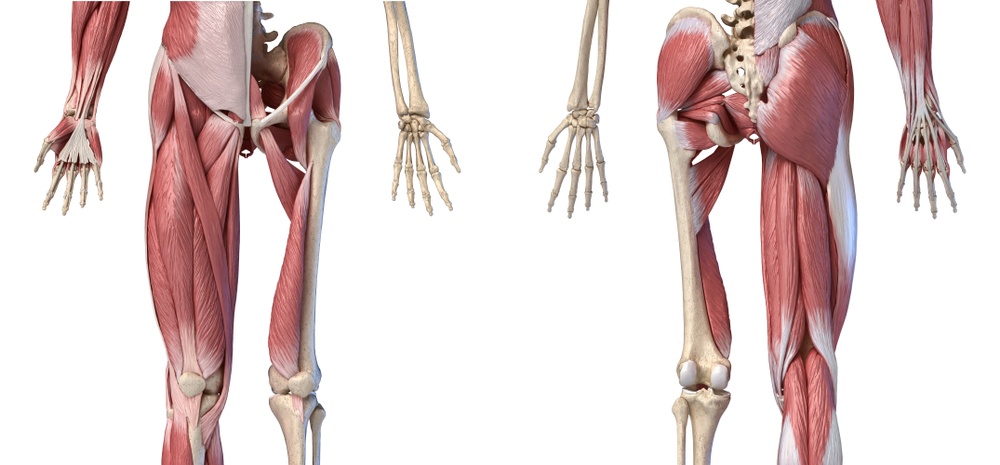

Una volta ristabiliti i corretti rapporti ossei, il paziente dovrà osservare un periodo di riposo (l’arto verrà immobilizzato con tutore), dopo di che dovrà seguire un programma di riabilitazione, al fine di rafforzare i muscoli che proteggono l’articolazione mantenendo saldo il femore all’anca (medio e grande gluteo, piriforme, otturatore esterno) e recuperare un corretto equilibrio neuromuscolare.

Purtroppo, a seguito di una lussazione, le strutture molli che circondano l’anca vengono più o meno gravemente lesionate: per questo motivo l’articolazione tende a rimanere instabile, predisponendo il paziente a recidive e a danni artrosici dovuti al mancato recupero del corretto equilibrio articolare.

Fondamentale, dopo il periodo di riposo prescritto dal medico, (come affermato nel paragrafo precedente) è rinforzare i muscoli stabilizzatori di questa importante articolazione.

Nel caso della lussazione dell’anca l’intervento si effettua sui muscoli grande e medio gluteo (si trattano in contemporanea). Questi muscoli rispondono in modo veramente eccellente e persistente al trattamento. L’esperienza ci dice che l’effetto può durare per anni senza ripetizione del trattamento.